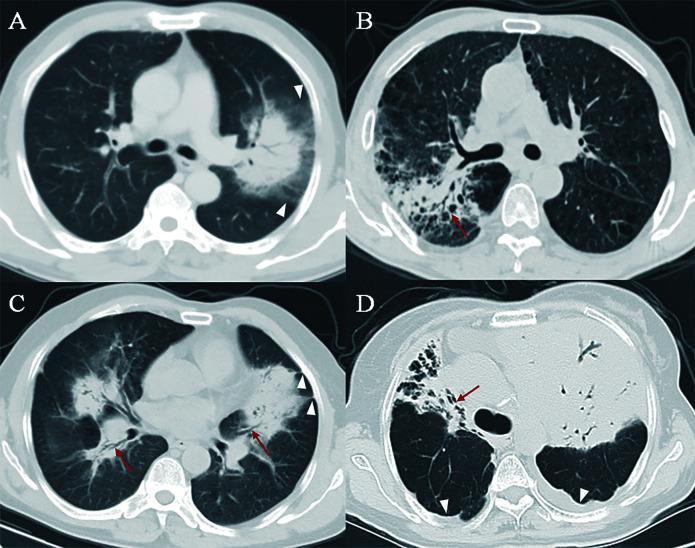

Pneumonia-like primary pulmonary lymphoma (PPL) was commonly misdiagnosed as infectious pneumonia, leading to delayed treatment. The purpose of this study was to establish a computed tomography (CT)-based radiomics model to differentiate pneumonia-like PPL from infectious pneumonia.

In this retrospective study, 79 patients with pneumonia-like PPL and 176 patients with infectious pneumonia from 12 medical centers were enrolled. Patients from center 1 to center 7 were assigned to the training or validation cohort, and the remaining patients from other centers were used as the external test cohort. Radiomics features were extracted from CT images. A three-step procedure was applied for radiomics feature selection and radiomics signature building, including the inter- and intra-class correlation coefficients (ICCs), a one-way analysis of variance (ANOVA), and least absolute shrinkage and selection operator (LASSO). Univariate and multivariate analyses were used to identify the significant clinicoradiological variables and construct a clinical factor model. Two radiologists reviewed the CT images for the external test set. Performance of the radiomics model, clinical factor model, and each radiologist were assessed by receiver operating characteristic, and area under the curve (AUC) was compared.

A total of 144 patients (44 with pneumonia-like PPL and 100 infectious pneumonia) were in the training cohort, 38 patients (12 with pneumonia-like PPL and 26 infectious pneumonia) were in the validation cohort, and 73 patients (23 with pneumonia-like PPL and 50 infectious pneumonia) were in the external test cohort. Twenty-three radiomics features were selected to build the radiomics model, which yielded AUCs of 0.95 (95% confidence interval [CI]: 0.94-0.99), 0.93 (95% CI: 0.85-0.98), and 0.94 (95% CI: 0.87-0.99) in the training, validation, and external test cohort, respectively. The AUCs for the two readers and clinical factor model were 0.74 (95% CI: 0.63-0.83), 0.72 (95% CI: 0.62-0.82), and 0.73 (95% CI: 0.62-0.84) in the external test cohort, respectively. The radiomics model outperformed both the readers' interpretation and clinical factor model ( P <0.05).

The CT-based radiomics model may provide an effective and non-invasive tool to differentiate pneumonia-like PPL from infectious pneumonia, which might provide assistance for clinicians in tailoring precise therapy.